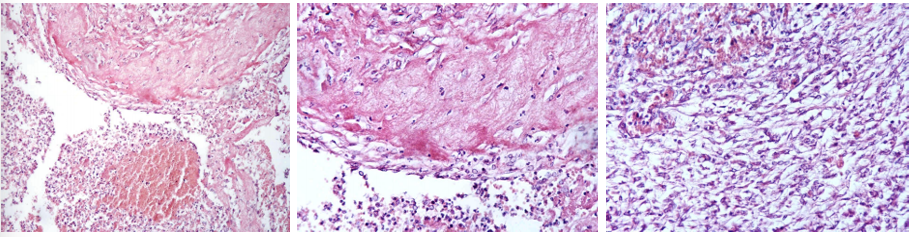

this is?

Pleuritis fibrosa/fibrinosa (repair by organization)

Description: On thoracic pleural surface. Pink-stained fibrin is infiltrated by macrophages (histiocytes), lymphocytes and neutrophils. Beneath there is young granulation tissue proliferating fibrin. Spaces between capillaries are filled with macrophages, lymphocytes, and elongated spindle-shaped fibroblasts.

Etiology: Pneumonia (lung parenchyma), thromboendocarditis (heart), fibrinous pleurisy (pleura) and other body tissues which have been sites of inflammation.

Pathogenesis: Repair by organization occurs when there’s an incomplete resolution of inflammation. Unabsorbed fibrin forms a scaffold for fibroblasts and capillary loops, so fibrosis develops in the area. Area doesn’t return to normal, but remains in a scarred state.

Fibrosis myocardii

Description: Myocardium of the heart is locally substituted by mature fibrous tissue with bright staining (some places fatty tissue is present). Substitution of damaged myocardium (infarct, necrosis, inflammation) by repair, when granulation tissue mature to highly-differentiated connective tissue (healing process).

Etiology: Damage from infarct, necrosis of different etiology and inflammation

Pathogenesis: Healing process begins with macrophages removing dead cells and debris, eliminating inflammatory exudate and dead tissue. The myocardial defect is filled with granulation tissue- fibroblasts, collagen-producing cells, and new blood vessels. This tissue matures into a fibrous scar, depositing collagen fibers for structural support. This restores structural integrity, but there may be a loss of function due to the replacement of specialized cells, determined by extent of loss.